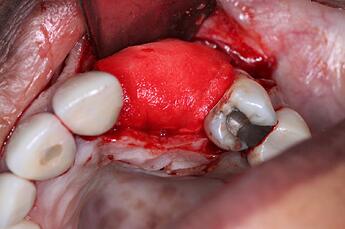

Missing 10 & 11 were extracted a year ago. Implants were placed, but healed terribly. The failed implants were removed, and now the site presents with significant bone loss, and severe resorption.

A Full thickness flap was reflected to expose the defect. You can see how severe the defect is, in both the vertical and horizontal dimensions. This is going to be a challenging GBR procedure, and we wanted to use the best materials at our disposal to encourage bone growth.